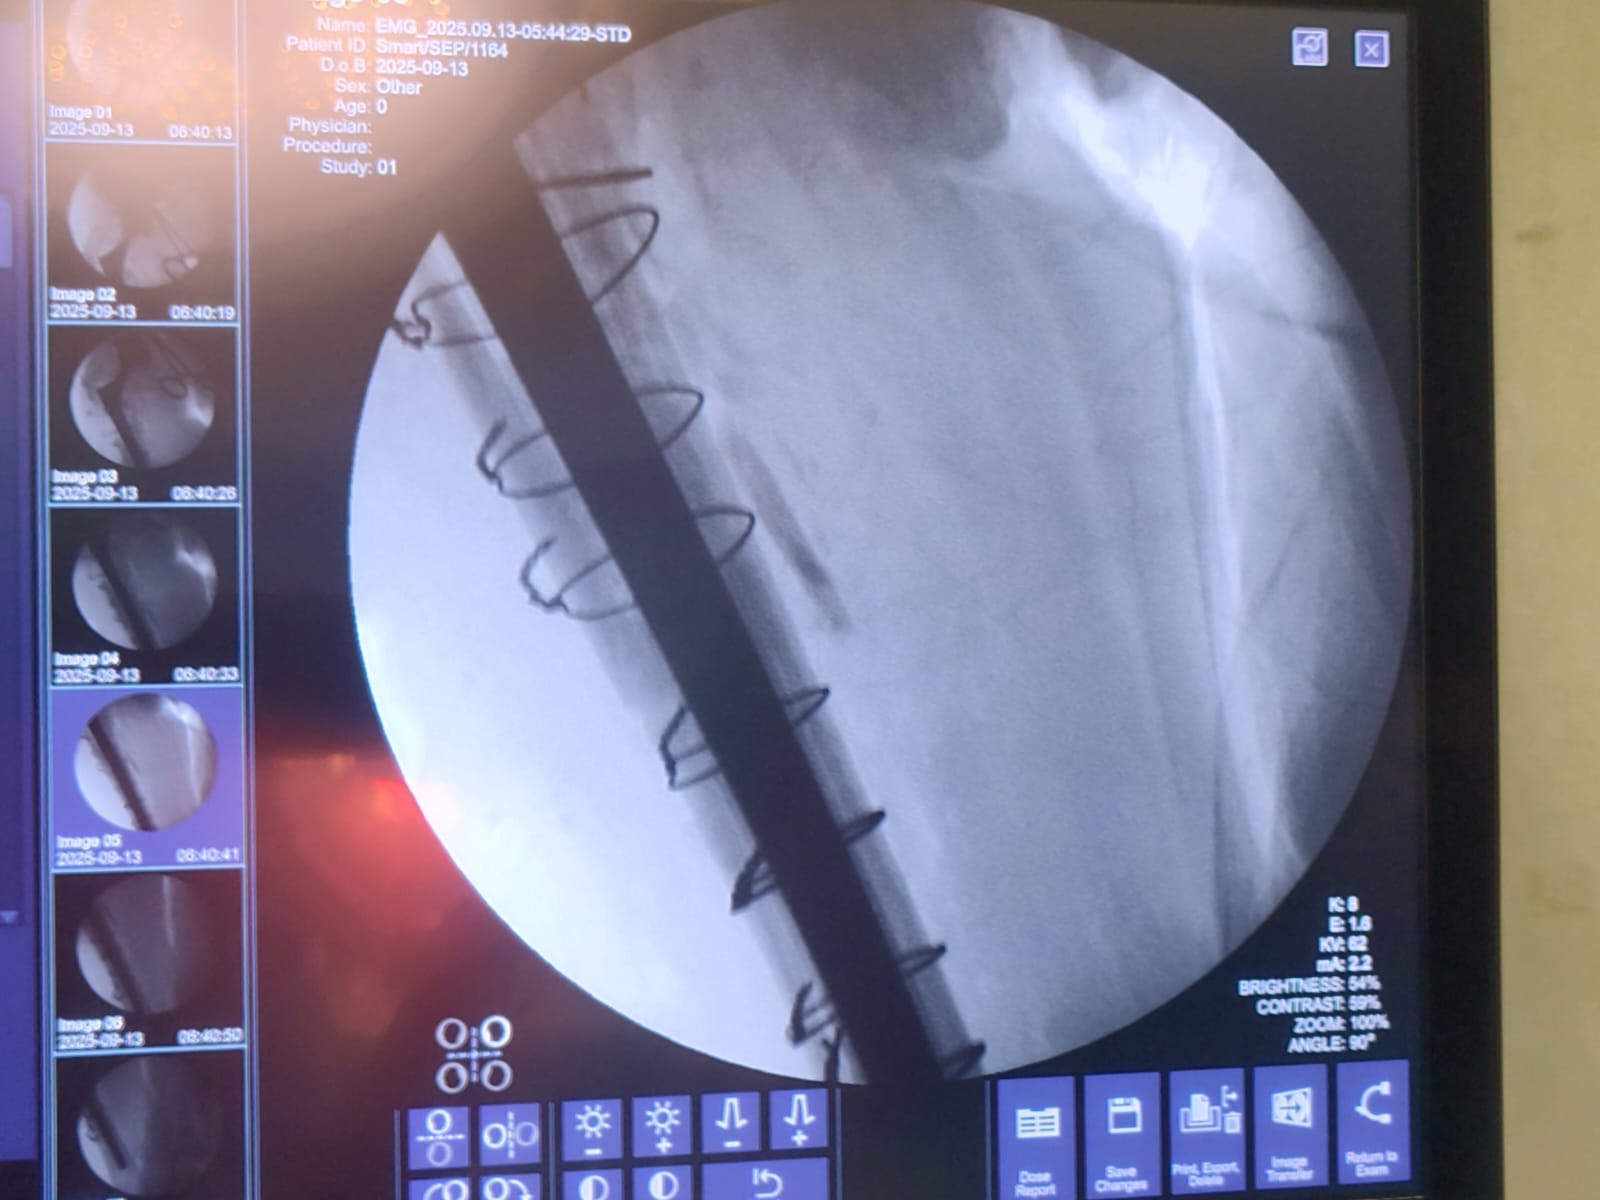

Dr Ajay Randive : IS MS Ortho (Mumbai) MRCSI ( UK) Consultant knee, Hip ,& Spine Surgeon, Dr Ajay Randhive is a eminent Knee, Hip , & Spine Surgeon practicing in to areas Andheri East,Santacruz East. Dr Ajay Randive did his MS Ortho residency from LTMMC, Sion Hospital Mumbai. He did overseas training in UK from 2003 till 2008. He is trained in total Knee Replacement, Hip Replacement, Revision Hip Replacement And Revision Knee Replacement Surgeries. He has worked at The Royal London Hospital. IN London where he worked a clinical fellow in joint Replacement unit. He has carried out more than 5000 Knee Replacement surgeries, 2500 Hip Replacement Surgeries, More Than 500 Revison Knee And Hip Replacement Surgeries 600 Spine surgeries & more than 1500 arthroscopic surgeries (Knee & Shoulder).